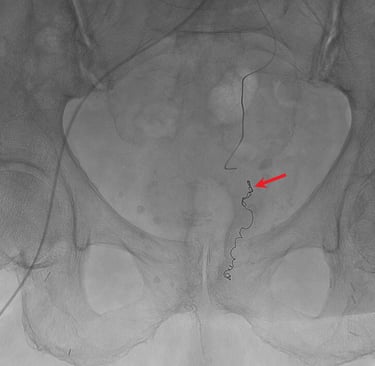

Exemple d'images d'embolisation hémorroïdaire réalisée dans le service.

Première image, à gauche : phase initiale de diagnostique avec le cathéter en place dans l'artère mésentérique inférieure (flèche blanche) retrouvant plusieurs artères rectales supérieures (flèches bleues) alimentant le plexus hémorroïdaire autour du canal anal (têtes de flèche orange).

Deuxième image, à droite : phase de traitement avec cathéter matériel d'embolisation (coils) en place dans une première artère rectale (flèche rouge).